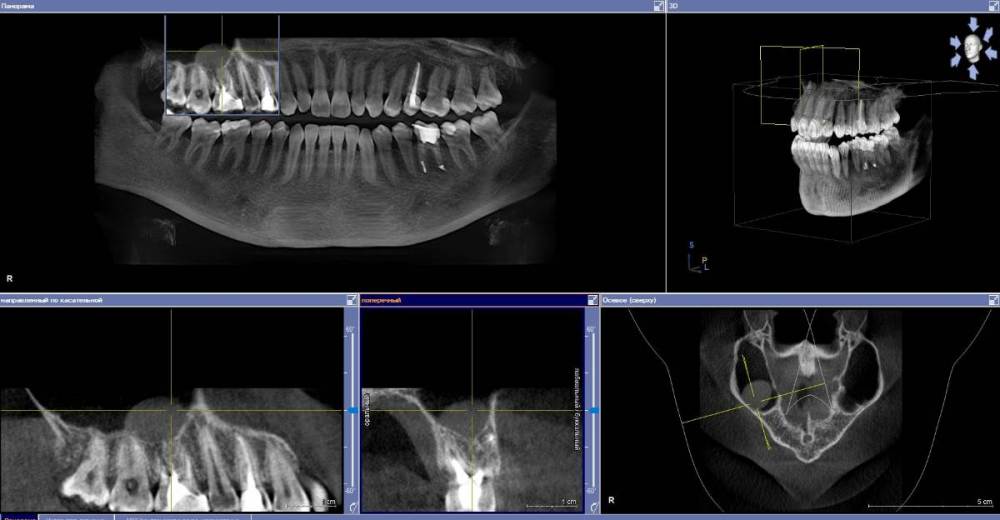

anishuma Опубликовано 1 сентября, 2021 Поделиться Опубликовано 1 сентября, 2021 (изменено) Здравствуйте, прошу помочь разобраться с моими КТ и направить для дальнейших действий. История такая: в 2018 году шестой зуб сверху справа был депульпирован. Долго сохранялись боли при нажатии, при жевании, зуб реагировал на холодной и горячее. Врач, который лечил, заверила что это постпломбировочные боли и скоро пройдет. Коронку побоялась ставить из-за этих болей. Затем примерно через год отлетел кусочек пломбы. Зуб восстановили для дальнейшей установки коронки. На данный момент есть ощутимая реакция на давление, при жевании, при чистки зубной щеткой. Зуб реагирует на холодное-горячее. Один врач сказал, что не видит показаний для перелечивания каналов. Другой врач настаивает на удалении зуба. Подскажите, пожалуйста, где истина, и возможно ли сохранить зуб. Изменено 1 сентября, 2021 пользователем anishuma Ссылка на комментарий

Bier Опубликовано 2 сентября, 2021 Поделиться Опубликовано 2 сентября, 2021 похоже что есть гранулема на корне 2 Ссылка на комментарий

St. Опубликовано 3 сентября, 2021 Поделиться Опубликовано 3 сентября, 2021 +1 к гранулеме. Я бы перелечивала каналы. Но нужно в процессе будет смотреть нет ли трещин в корне. Ссылка на комментарий